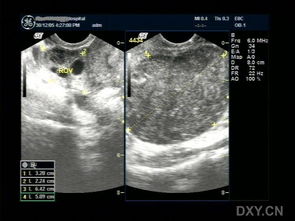

不知道您說(shuō)的子宮左側(cè)是宮腔內(nèi)的腫塊還是附件的腫塊,如果是子宮腔內(nèi)的那么就是子宮肌瘤,而且肌瘤已經(jīng)相對(duì)較大了,需要早期的手術(shù)治療,建議您可以根據(jù)肌瘤的具體位置選擇合適的手術(shù)方法,粘膜下和肌壁間肌瘤采用奧洛克超導(dǎo)多彈頭系統(tǒng)治療,這種方法不需要開(kāi)刀不需要住院,損傷小,腹部沒(méi)有任何瘢痕,可以保留子宮和生育能力,如果是漿膜下建議采用宮腹腔鏡方法治療,如果是附件的囊腫,那么也建議早期手術(shù),以免劇烈活動(dòng)會(huì)引起囊腫的扭轉(zhuǎn)發(fā)生大出血,囊腫的治療首先需要確診囊腫的性質(zhì),可以采用奧洛克導(dǎo)航微電極系統(tǒng)或者腹腔鏡方法治療,詳細(xì)的情況建議您先確診具體是什么情況,然后選擇合適的治療方法,祝您早日康復(fù)!